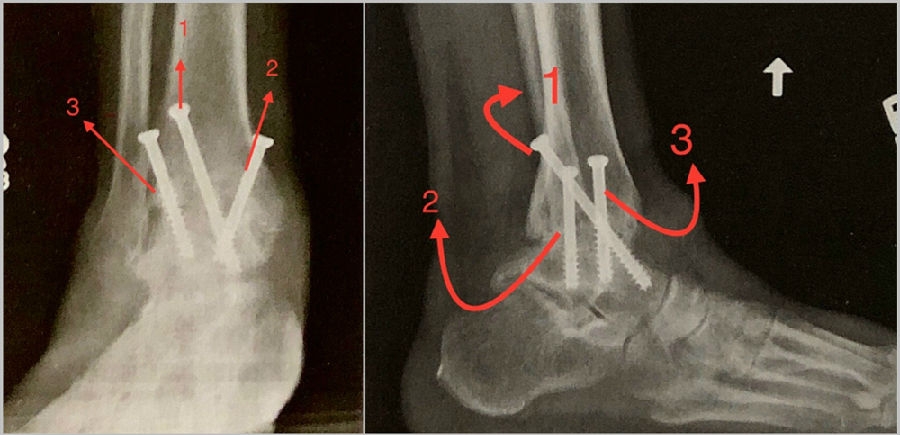

3. 导针引导下置入6.5-8.0mm空心钉固定,置入3枚,第一枚螺钉起自胫骨后外侧,远端至距骨头颈区域 。

第二枚打入内侧近端螺钉,向后进入距骨体。

第三枚螺钉从近端前外侧指向远端内侧方向。

第1枚螺钉自内踝后侧向前下方向打入距骨头颈部;

第2枚螺钉自前内踝斜向下至距骨体部;

第3枚螺钉自胫骨远端前外侧向距骨体后内侧。